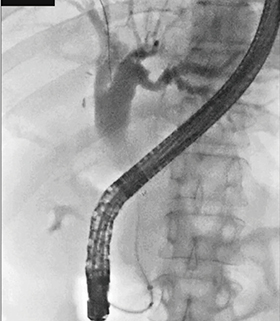

症例2は膵頭部がんの多発肝転移症例である。金属ステント留置後、化学療法により腫瘍が縮小し、留置5か月後にステントの逸脱が生じた(図6)。化学療法を継続し、re-interventionが必要になったが、上十二指腸角(SDA)が狭窄していたため、ガイドワイヤとカテーテルを先進させてナビゲーションしつつ、愛護的にストレッチをかけてガイドワイヤを十二指腸下行脚に到達させた。乳頭との距離をとることが困難であったが、以前にESTを行っていたため無事にステントを留置できた(図7)。

図7 症例2:初回留置から12か月後に金属ステントの再留置を実施

パルスレート7.5fps、線量モード:Mid